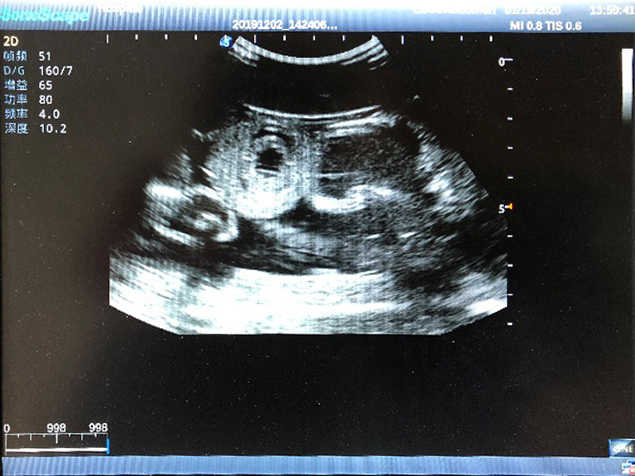

2)  High quality ultrasound image with clear structures like gallbladder, liver, intestines, arteries and veins etc.

4)  ltrasound gallbladder pathologies like cholecystitis, gallstone and polypoid degeneration

5)  Normal & pathological ultrasound live and intestine models inside